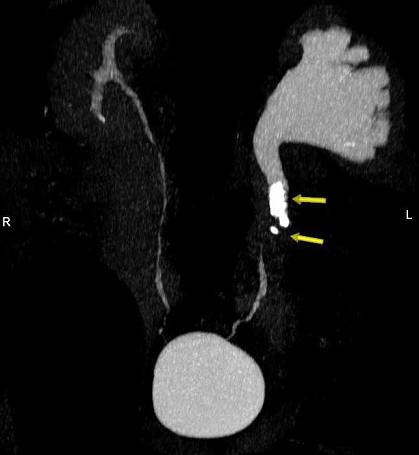

问题 男,42岁,反复左侧腰部疼痛伴血尿3个月余,CT检查如图,下列说法错误的是 ( )

选项 A、左输尿管结核并左肾积水 B、考虑为左输尿管结石并积水 C、左侧输尿管上段扩张 D、左侧肾盂肾盏扩张 E、左侧输尿管内可见多发的高密度影

答案 A